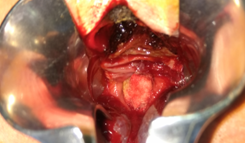

Μπλε βέλος — Έκθεση του ορθού. Είσοδος στον προϊερό χώρο από τα δεξιά (Ευγενική παραχώρηση Dr. V. Penopoulos)